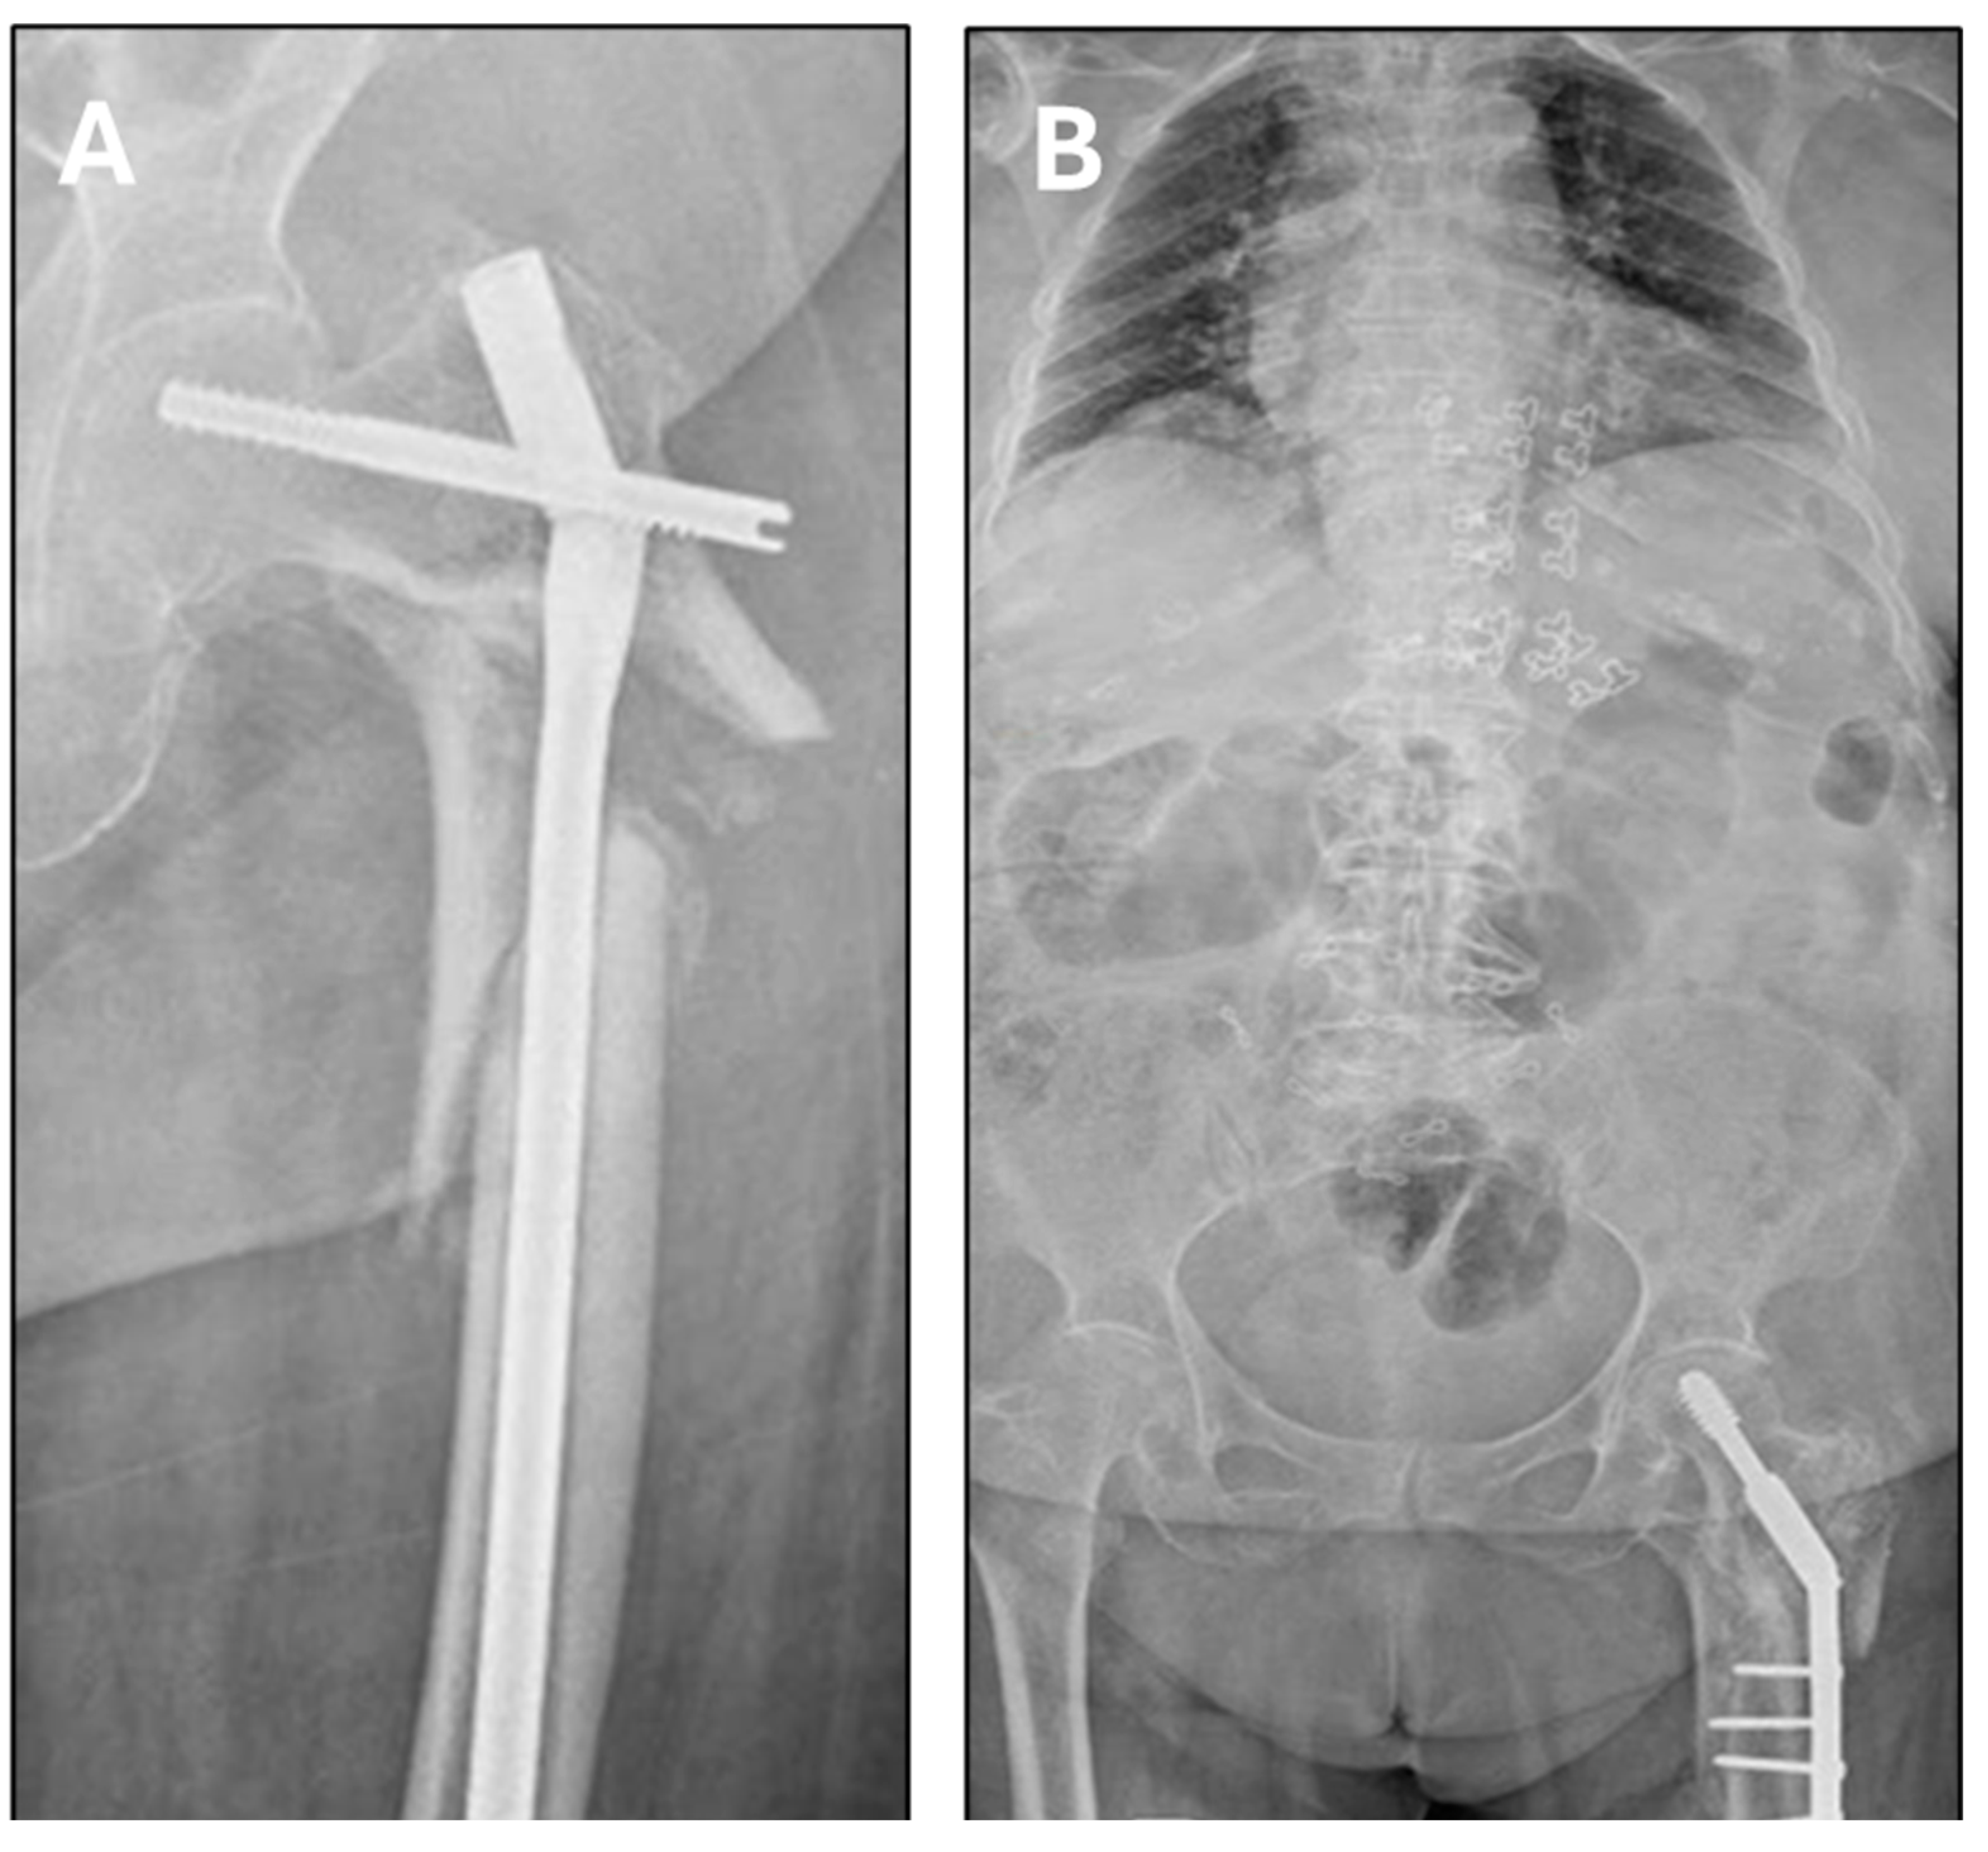

| DHS degrees used $ | 135° | 150° | 150° | 135° | 150° | 150° |

| Femoral neck angle post-surgery * | 142° | 150° | 150° | 147° | 145° | 146.8 (142–150) |

| Post-surgery offset (mm) * | 24 | 19 | 18 | 20 | 17 | 19.6 (17–24) |

| Vertical distance nonunion–head post-surgery (mm) * | 65 | 55 | 38 | 52 | 48 | 51.6 (38–65) |

| Postoperative leg lengthening (mm) * | 8 | 12 | 6 | 6 | 8 | 8 (6–12) |